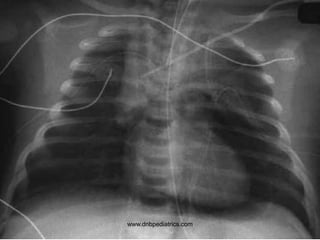

Questions

1. What is the diagnosis?

2. What is the clinical sign for the diagnosis

called as?

3. Name one intervention which can lead to

this?

1. Pneumopericardium

2. Hammans sign

3. Invasive ventilation with high pressures